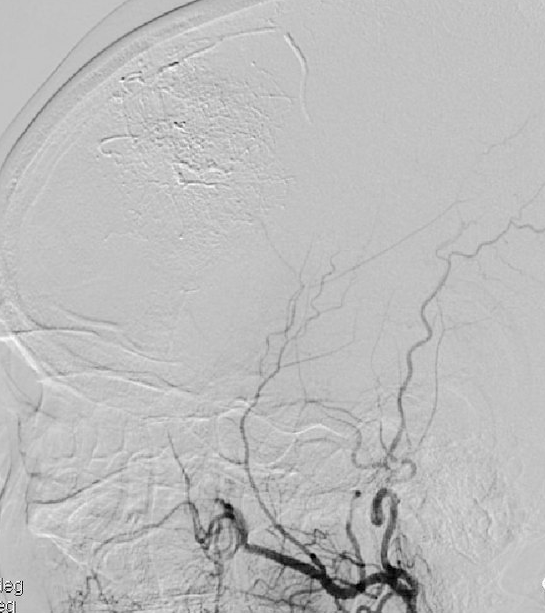

▲脑血管造影显示肿瘤血供丰富

▲介入栓塞责任动脉

经过详细的颅脑增强磁共振检查发现吴阿姨为左侧额部巨大镰旁脑膜瘤,必须要尽快手术治疗,但肿瘤位于功能区旁且体积巨大,血供丰富,手术难度大、风险高,稍有不慎即可引起患者肢体偏瘫、失语、昏迷甚至危及生命可能。我院神经外科学科带头人王鹏副院长组织了术前多学科讨论,因肿瘤血供丰富,体积巨大,直接手术治疗面临术中失血多、手术时间长等困难,最终决定由神经外科介入团队先行介入栓塞治疗后再进行开颅脑膜瘤切除术。

术前与吴阿姨及家属充分沟及取得同意后,神经外科团队在王鹏副院长的带领下,由介入团队在全麻下先行经导管颅内血管栓塞术,后行开颅左额部镰旁巨大脑膜瘤切除术,术中在显微镜下,王院长带领神经外科团队成功全切肿瘤。